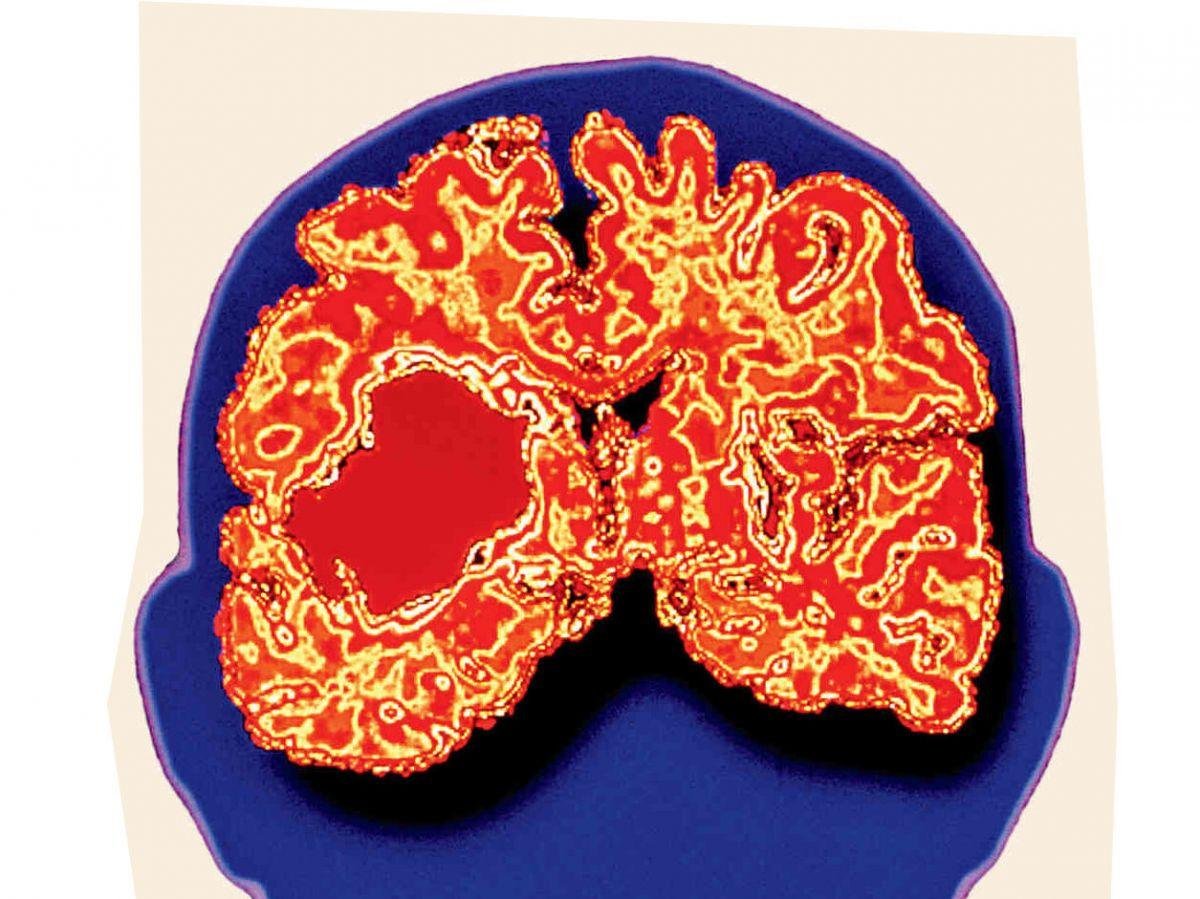

Si elle ne représente que 20% des cas, l’hémorragie cérébrale est la forme la plus mortelle d’AVC. Elle intervient lorsqu’un vaisseau se rompt dans le cerveau et qu’un hématome se forme. Un programme de recherche prometteur lancé cet été à Lille entend renouveler l’approche thérapeutique en intervenant aux étapes clés de l’hémorragie. Explications.[Lire l'article en intégralité]